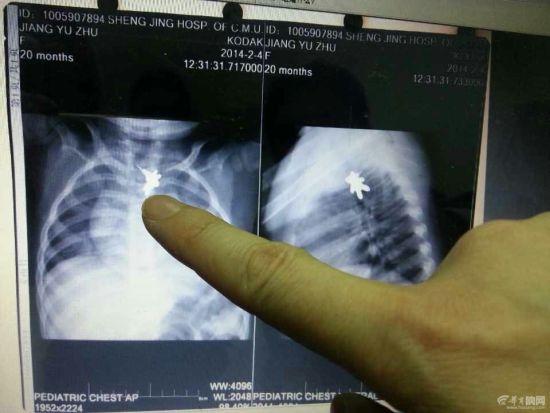

孩子吞下的耳钉。

卡在孩子食道里。

21时30分许,孩子被转入沈阳军区总医院,内窥镜科副主任高飞见女童一直淌口水,就判断黏膜肿了,导致孩子喉咙疼,不敢吞咽口水。高飞给她做了详细检查,在影像中显示,耳钉就卡在食管第二狭窄处,黏膜肿了,把耳钉都包了起来。